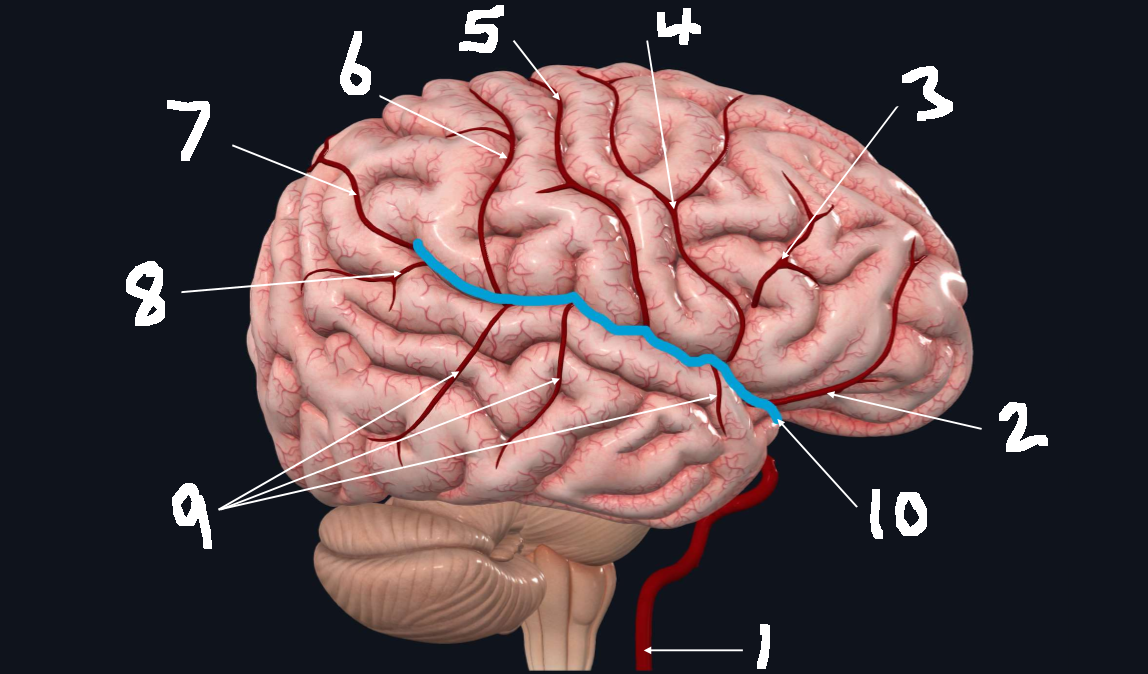

What is 1?

internal carotid artery

What is 2?

orbitofrontal artery

What is 3?

prefrontal artery

What is 4?

precentral artery

What is 5?

central artery

What is 6?

postcentral artery

What is 7?

posterior parietal artery

What is 8?

angular artery

What is 9?

temporal arteries (anterior, middle, posterior)

What is 10?

lateral cerebral fissure